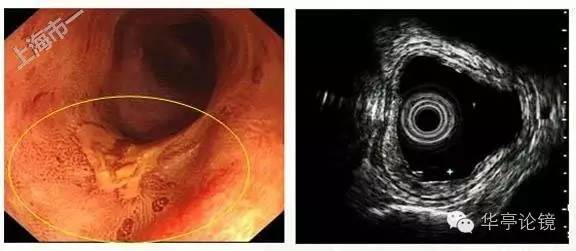

白光内镜:距门齿25-28cm处见病变区粘膜发红,表面粗糙,分支血管网消失,病变约占环周面积3/4,与周围正常粘膜分界清晰。卢戈氏碘染色见病变处粘膜脱染。

ME-NBI内镜:病变处见背景着色,IPCL呈V1-V3型改变,预测病变深度可达m3-sm1。